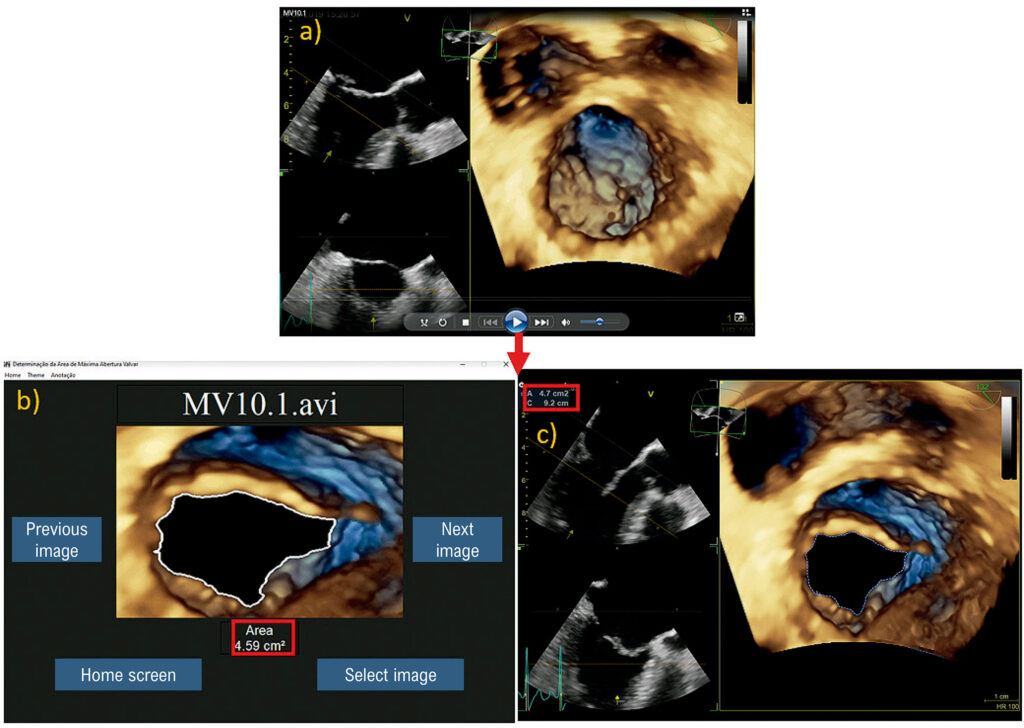

Automatizar o processo de determinação da área de abertura máxima da valva mitral, por meio da aplicação de Processamento Digital de Imagens (PDI) em exames de ecocardiograma, desenvolvendo um algoritmo aberto com leitura de vídeo no formato avi.

Este estudo piloto observacional transversal foi realizado com vinte e cinco exames diferentes de ecocardiograma, sendo quinze com abertura normal e dez com estenose mitral reumática. Todos os exames foram realizados e disponibilizados por dois especialistas, com autorização do Comitê de Ética em Pesquisa, que utilizaram dois modelos de aparelhos ecocardiográficos: Vivid E95 (GE Healthcare) e Epiq 7 (Philips), com sondas multiplanares transesofágicas. Todos os vídeos em formato avi foram submetidos ao PDI através da técnica de segmentação de imagens.

As medidas obtidas manualmente por ecocardiografistas experientes e os valores calculados pelo sistema desenvolvido foram comparados utilizando o diagrama de Bland-Altman. Observou-se maior concordância entre valores no intervalo de 0,4 a 2,7 cm2.

Foi possível determinar automaticamente a área de máxima abertura das valvas mitrais, tanto para os casos advindos da GE quanto da Philips, utilizando apenas um vídeo como dado de entrada. O algoritmo demonstrou economizar tempo nas medições quando comparado com a mensuração habitual.